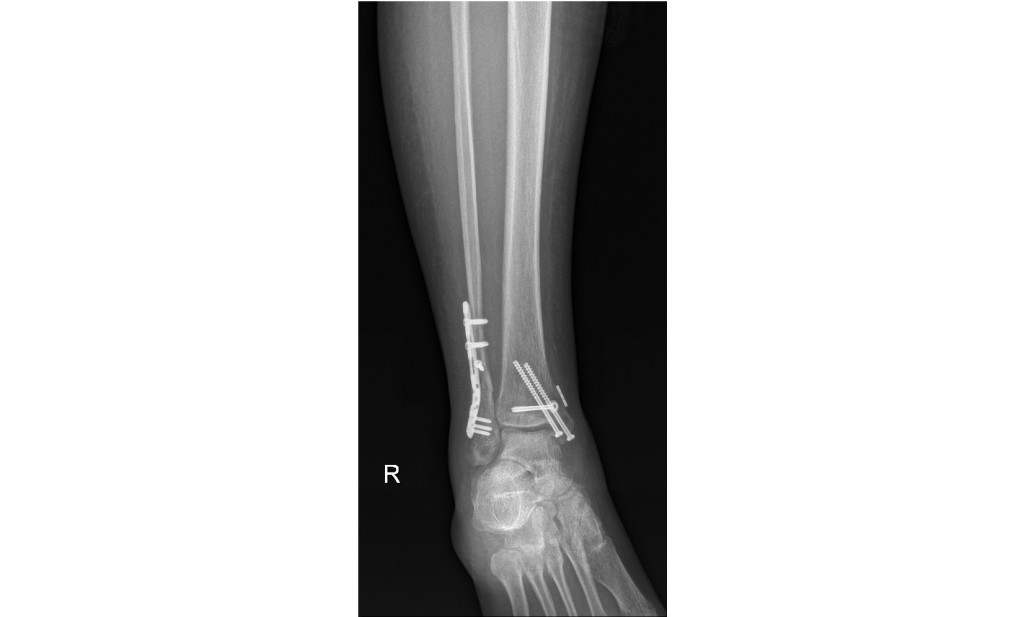

She has 9 screws, a self tensioning fixator and a 6" metal plate in her ankle.

Here's what my wife's ankle looks like: